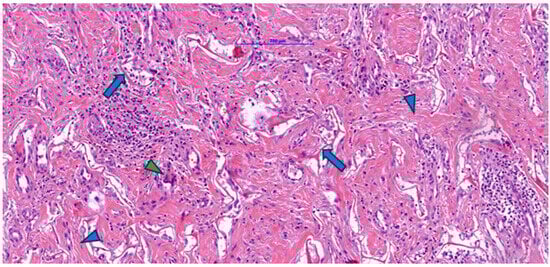

Associated with these structures, dispersed fibroblastic cells with a fusiform appearance and elongated nuclei were arranged parallel to the collagen fibers, indicating active cellular colonization and endogenous collagen deposition. The examined fragment showed pale/clear lacunae—empty spaces corresponding to initial pores or areas where the matrix had been partially degraded—some lined by cells with mesenchymal features, suggesting ongoing integration. Figure 1 illustrates minimal inflammation with rare perivascular mononuclear cells, whereas Figure 2 shows foci of inflammatory infiltrate composed of lymphocytes, macrophages, and plasma cells, as well as multinucleated foreign-body-type giant cells.

Figure 2. Post-implantation dermal tissue fragments with Integra in the neovascularization phase showed remnants (arrow) of eosinophilic material (Integra), numerous collagen fibers (blue arrowhead), and a prominent lymphocytic, plasmacytic, and macrophage inflammatory infiltrate, including multinucleated giant cells (green arrowhead).